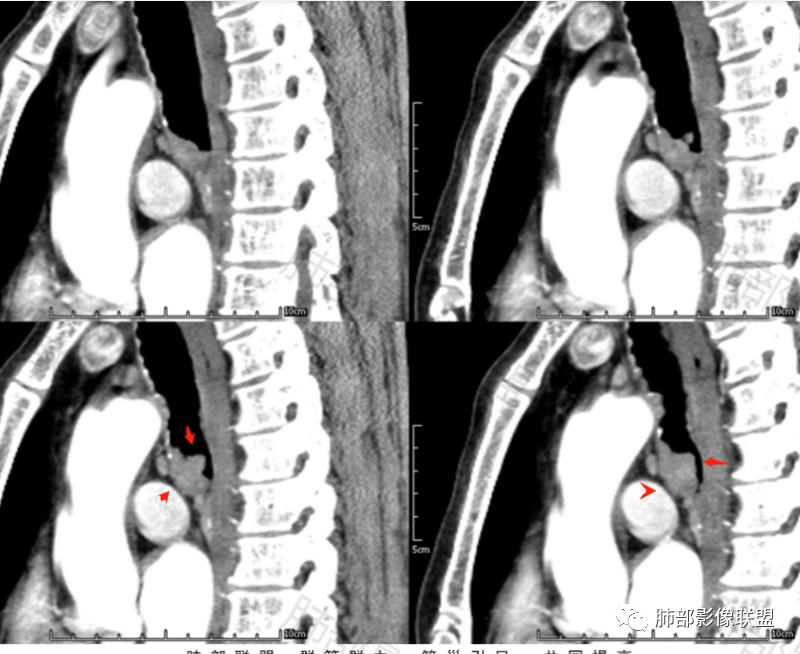

晨读57岁的男性病人,病史一周,以咳嗽咳痰痰中带血为主要表现, CT扫描与支气管分叉偏左侧支气管的位置上见分叶状的一个结节影,并局部凸向管腔内,支气管管腔明显的变窄, 病灶以实性为主,周围斑点状的钙化,生长支气管内外侧壁,可见“冰山征”,增强扫描比较明显的强化,肿块未见坏死,周围无明显肿大淋巴结。考虑支气管来源的占位。类癌?鳞状细胞癌?鉴别:支气管息肉?硬化性血管瘤?

晨读:老年男性,气管腔内外肿块累及左主支气管(跨壁生长、局部钙化中断,以腔内成分为主),形态不规则,增强以延迟强化明显(含纤维或平滑肌成分)、无坏死,纵隔淋巴结肿大,考虑MT,1. 老年男性吸烟史,鳞癌肯定需要考虑(但延迟强化似乎不十分支持),2. 腺样囊腺癌(应环状生长为主、无囊变);3.类癌(应:腔外大于腔内、强化不十分支持);4.肉瘤类,软骨肉瘤不支持,纤维肉瘤或平滑肌肉瘤罕见。综合:鳞癌>纤维或平滑肌肉瘤>类癌。

二、影像表现:肿瘤好发于气管后壁软骨和膜部连接处,这与该部位黏液腺较多有关,沿气管粘膜下延伸,呈腔内息肉样或宽基底的软组织密度肿块,沿管壁梭形生长,长径大于短径(具有粘膜下浸润生长的特性所致),管壁弥漫或全周增厚,伴管腔不同程度狭窄,肿瘤可同时侵犯腔内外,形成腔内外软组织肿块。平扫密度均匀,呈软组织密度,瘤内坏死钙化少见。增强后病灶呈不同程度均匀或不均匀轻中度强化,肺内转移常见。

2.类癌:典型类癌绝大多数为中央型。对于成年人,更常见于女性。累及主、叶、段支气管,远端朝外侵犯,一般不是周围环形壁增厚;腔内外生长-冰山征;血供丰富、显著强化,可有钙化。